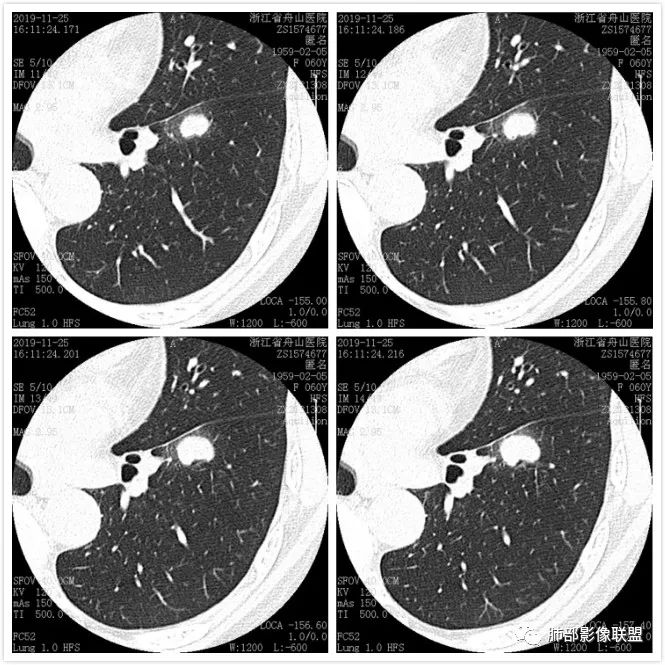

肺腺癌1例CT影像讨论

图像资料

这个病例看上去像个爱心,但是具备恶性征象不少,有分叶,脐凹,支气管截断,膨隆,月牙铲等。没有毛刺,牵拉力不强,多见于低分化肿瘤,其收缩力可以消失,特别是实体型。实体型内部纤维组织很少。与不典型类癌鉴别比较难,典型类癌分叶不明显;不典型类癌男女比例差不多,少见。

图一:提示支气管截断;图二:看到脐凹血管进入;图三:月牙铲;图四:典型分叶;图五:病灶膨隆,图六:支气管截断可能。 医学百科网 | YxBaike.Com